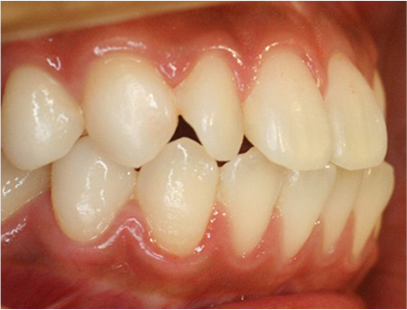

• 左側

• 右側